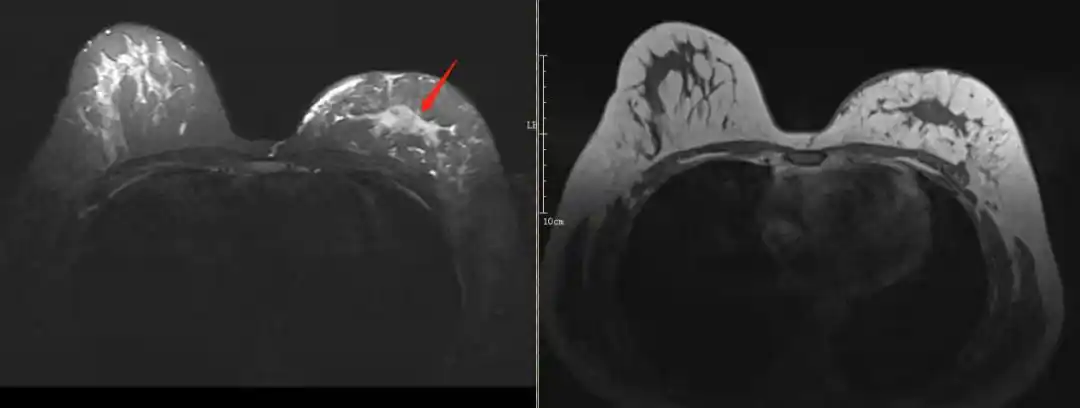

磁共振检查对恶性肿瘤的敏感度比较高,通过时间剂量曲线能够让医生对

mri筛查能筛出更早期的乳腺癌

对比增强能谱成像与动态增强磁共振成像诊断乳腺癌的对比研究

磁共振乳腺影像报告和数据系统